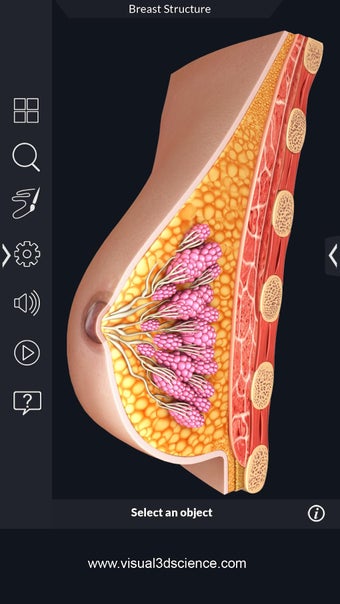

Met deze applicatie kun je 360° draaien rond een zeer realistisch 3D-model van het menselijk lichaam. Je kunt in- en uitzoomen op elk deel om er beter naar te kijken.

De camera kan worden verplaatst om een ander beeld van elk deel te krijgen.

Je kunt alle informatie over de organen krijgen, inclusief hun locatie, hun functie en hoe ze eruitzien.